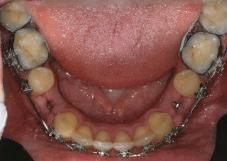

8 Dental Tribune Bulgarian Edition / октомври 2022 г. По време на лечението Фиг. 21 Фиг. 25 Фиг. 30 Фиг. 31 Фиг. 34 Фиг. 38 Фиг. 40 Фиг. 44 Фиг. 48 Фиг. 50 Фиг. 49 Фиг. 46 Фиг. 39 Фиг. 41 Фиг. 45 Фиг. 47 Фиг. 42 Фиг. 43 Фиг. 35 Фиг. 36 Фиг. 37 Фиг. 32 Фиг. 33 Фиг. 26 Фиг. 28 Фиг. 29 Фиг. 27 Фиг. 22 Фиг. 23 Фиг. 24

7Dental Tribune Bulgarian Edition / октомври 2022 г. Преди лечението Фиг. 1 Фиг. 4 Фиг. 7 Фиг. 10 Фиг. 13 Фиг. 16 Фиг. 17 Фиг. 18 Фиг. 19 Фиг. 20 Фиг. 11 Фиг. 14 Фиг. 12 Фиг. 15 Фиг. 8 Фиг. 9 Фиг. 5 Фиг. 6 Фиг. 2 Фиг. 3